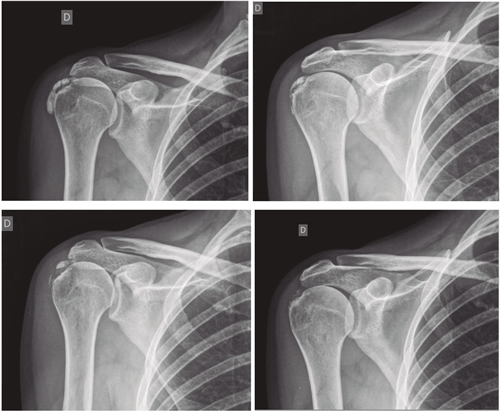

El número promedio de sesiones en nuestra serie fue de 20. El criterio para continuar o suspender el tratamiento fue la evolución radiológica y clínica (Figuras 4 y 5). Las intervenciones se realizaron hasta un máximo de 40 sesiones. Perrón trató a sus pacientes por 9 sesiones (3 sesiones semanales por 3 semanas) (14). Leduc trató con 10 sesiones (3 por semana las dos primeras semanas; y luego una semanal por 4 semanas) (15). Rioja-Toro trató a sus pacientes por 40 sesiones (5 veces por semana) y los evaluó a las 20 y a las 40 sesiones (3). Chico-Álvarez trató a sus pacientes entre 15 y 30 sesiones dependiendo de la evolución radiológica (5 veces por semana) (1).

Fig. 4. Paciente mujer de 47 años con tendinitis calcificante de supraespinoso derecho, de tipo formativa, quien tras 30 sesiones de iontoforesis disminuyó el dolor medido por EVA de 6/10 a 3/10 y la calcificación de 38 mm a 8 mm (valoraciones al inicio, a las 10, a las 20 y a las 30 sesiones, respectivamente).

El estudio que se ha realizado es cuasiexperimental tipo antes-después, e incluyó a 138 pacientes. Perrón (14) realizó un estudio experimental randomizado (n = 11 grupo experimental; n = 10 grupo control), lo mismo que Leduc (15) (n = 17 grupo experimental; n = 10 grupo control). Rioja-Toro (3) realizó un estudio experimental tipo antes-después a 34 pacientes (n = 34). Chico-Álvarez (1) realizó un estudio experimental randomizado (n = 25 grupo experimental 1; n = 25 grupo experimental 2; n = 25 grupo experimental 3).

Fig. 5. Paciente mujer de 44 años, con tendinitis calcificante de supraespinoso izquierdo, de tipo resortivo, quien tras 20 sesiones de iontoforesis disminuyó el dolor medido por EVA de 10/10 a 4/10, y la calcificación de 22 mm a 0 mm (desaparición completa).